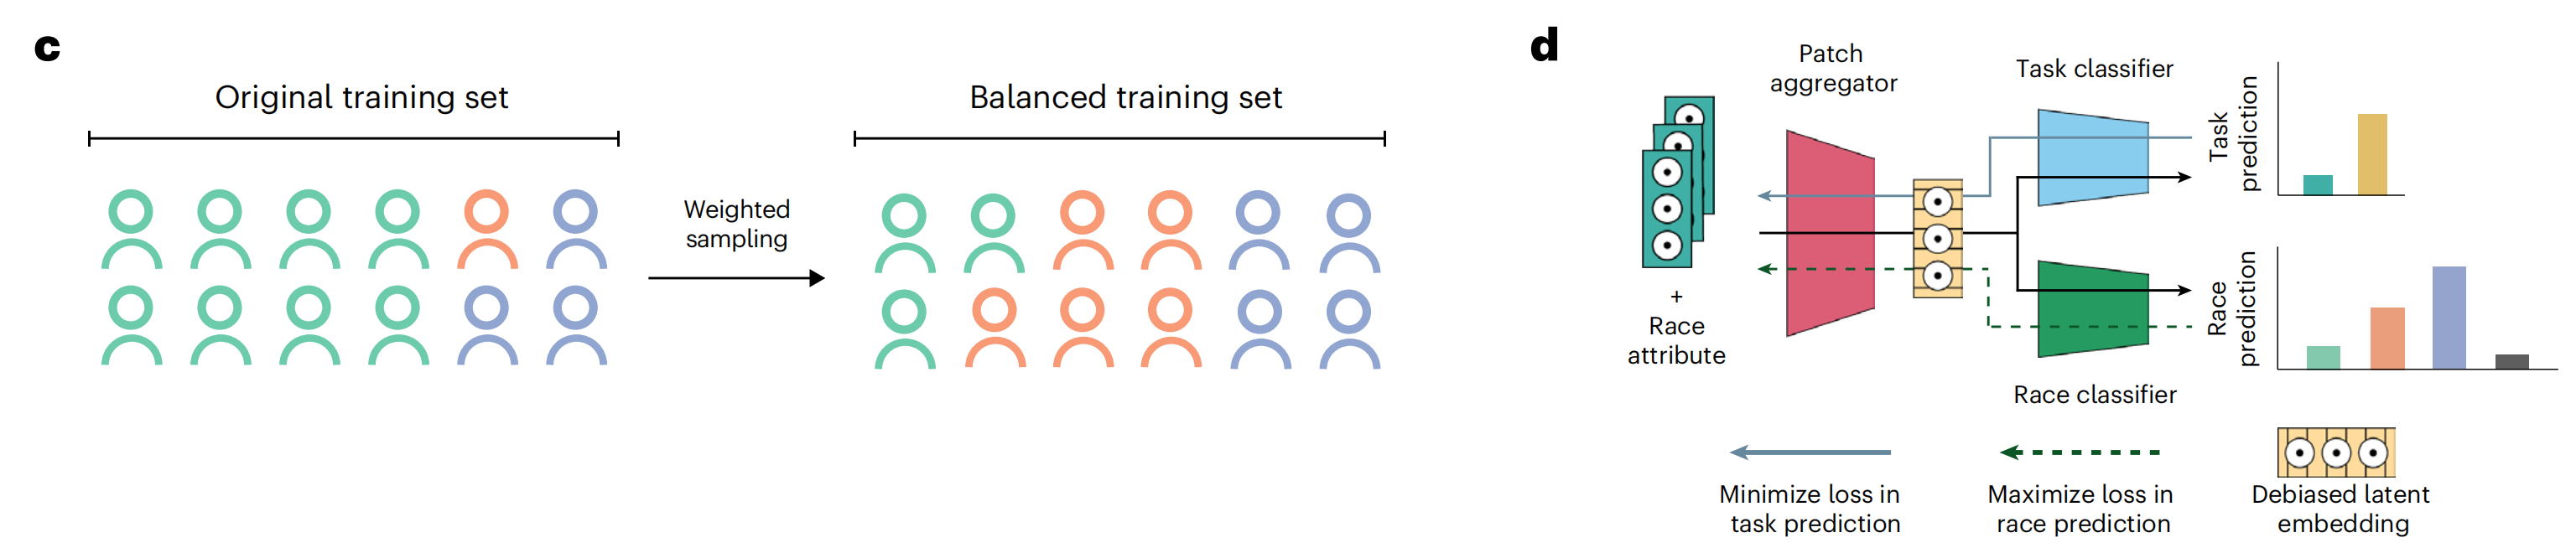

这篇文章发表在《Nature Medicine》2024年4月号上,题为《Demographic bias in misdiagnosis by computational pathology models》,作者包括Anurag Vaidya, Richard J. Chen, Drew F. K. Williamson等多位研究人员。文章主要探讨了在计算病理学模型中,人口统计因素对性能的影响,尤其是这些模型在对乳腺癌和肺癌亚型分类以及胶质瘤中IDH1突变预测时,对不同人群可能存在的偏见和误差。

文章指出,尽管计算病理学系统获得了越来越多的监管批准,但基于深度学习的系统经常忽视人口统计因素对性能的影响,可能导致偏见。这一问题尤为重要,因为计算病理学依赖于大型公共数据集,而这些数据集往往不能充分代表某些人群。研究使用了来自癌症基因组图谱(The Cancer Genome Atlas, TCGA)和EBRAINS脑肿瘤图谱的公开数据,以及内部患者数据,展示了在不同人群之间存在显著的性能差异。

研究结果表明,使用常见的建模方法时,白人和黑人患者在乳腺癌亚型分类、肺癌亚型分类以及胶质瘤中IDH1突变预测方面的性能差距分别为3.0%、10.9%和16.0%。研究发现,通过自监督视觉基础模型获得的丰富特征表示可以减少群体间性能差异。即便如此,自监督视觉基础模型并不能完全消除这些差异,这突显了在计算病理学中持续需要努力减轻偏见。

文章还讨论了数据特征、模型架构和偏见缓解策略对模型公平性和性能的影响,并建议监管和政策机构在评估指南中整合人口统计分层评估。此外,研究还发现,即使在考虑了与人群相关的数据特征后,不同种族群体之间的性能差异仍然存在,这表明需要在计算病理学中进一步研究和解决这些差异。

文章最后强调,为了提高计算病理学模型的公平性和性能,需要采取多种措施,包括使用自监督学习、改进数据预处理技术、实施偏见缓解策略,并确保在不同人群中进行充分的模型评估和测试。

Fig. 1 展示了在研究中使用的三个数据集(TCGA、MGB和EBRAINS脑肿瘤图谱)的特征、研究中使用的公平性指标以及建模选择。

以下是对图的详细分析:

a 部分展示了用于研究的三个数据集的组成,包括它们包含的用于诊断算法研究的幻灯片数量。这些数据集用于调查在最小化行动学习(MIL)幻灯片级别癌症诊断算法中的人口统计偏差,具体是针对乳腺癌和肺癌亚型分类以及胶质瘤中IDH1突变预测。研究使用了种族分层的ROC AUC(接收者操作特征曲线下面积)、TPR差异(真正例率差异)和独立测试队列上的种族预测来调查差异。

b 部分描述了MIL计算病理学研究中使用的深度学习(DL)管道的不同阶段,包括组织分割和贴片、使用贴片编码器映射到低维表示,以及分类。图中还展示了与公平性相关的技术,包括控制批次效应和测试集偏差、建模选择和偏见缓解策略。

c 和 d 部分介绍了研究中使用的两种常见的偏见缓解策略。c 部分描述了重要性加权(IW),这是一种通过与它们在总人口中的大小成反比地对种族群体中的患者进行采样,以确保公平代表性的方法。d 部分描述了对抗性正则化(AR),这是一种通过使嵌入对种族不可知来缓解偏见的策略。通过最大化辅助种族分类器的损失来实现这一点。

总体而言,Fig. 1 提供了对研究中使用的数据集、评估方法和偏见缓解策略的全面视图,并通过可视化手段展示了不同技术对减少种族间性能差异的潜在影响。